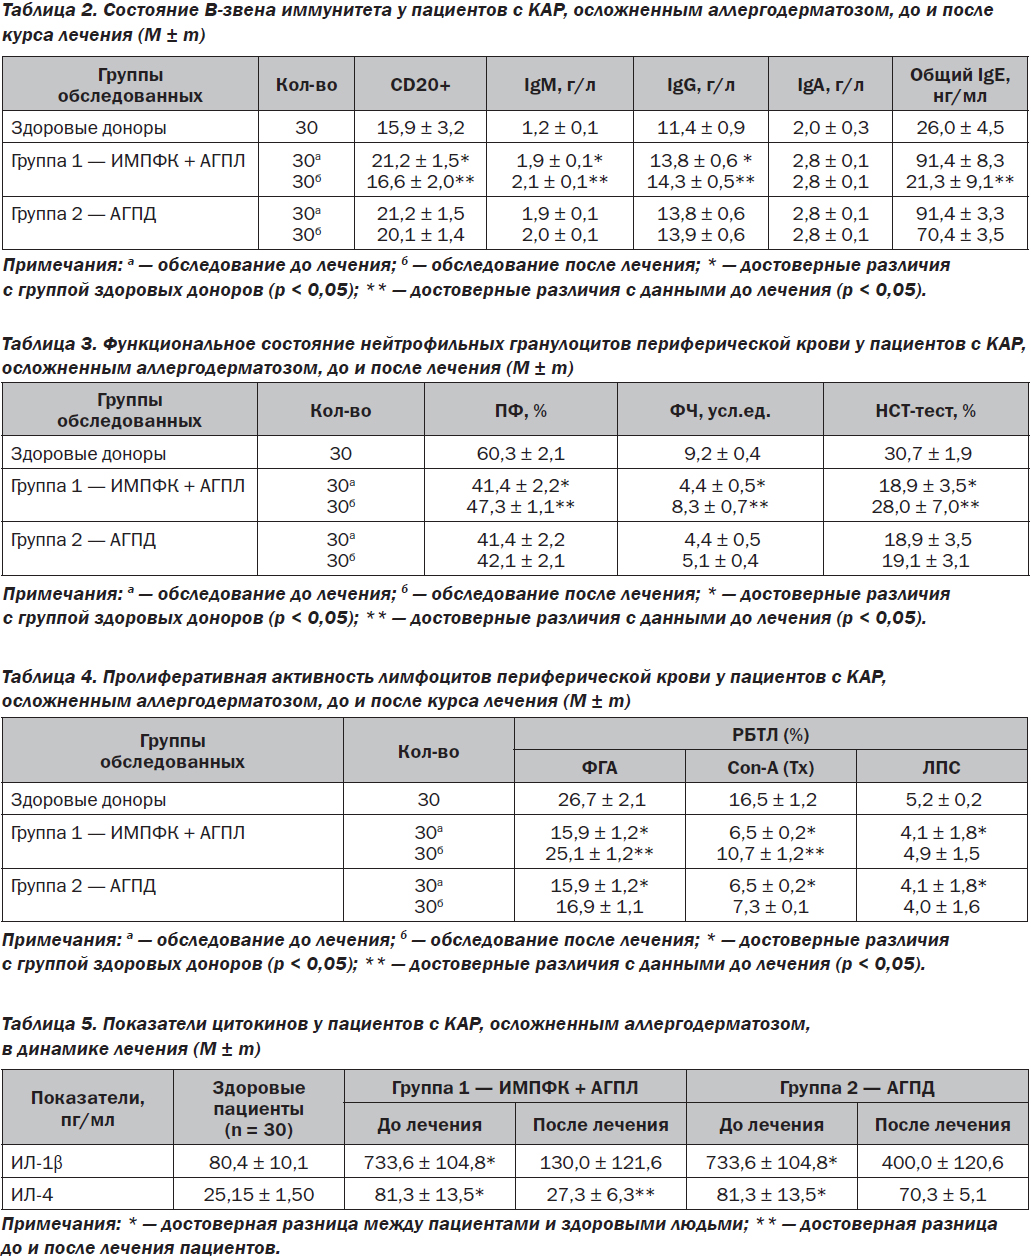

У пациентов первой группы, лечившихся ИМПФК + АГПЛ, обращает на себя внимание нормализация ИЛ-4 и увеличение количества ИЛ-1β, что объясняется большим количеством аллергенов, попавших в организм человека. Это является одним из проявлений защитной функции организма человека и специфического иммунитета.

ИМПФК + АГПЛ имеют преимущество перед препаратами АГПД в лечении аллергодерматозов, имеющих склонность к хронизации процесса, что подтверждается нормализацией ИЛ-4, показателей фагоцитоза.